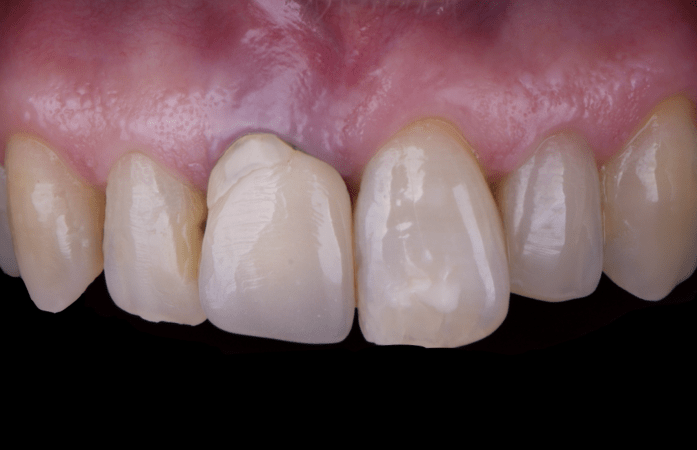

After an appropriate healing period, the definitive prosthesis was planned and delivered. A screw-retained zirconia crown was fabricated to ensure long-term durability, optimal esthetics, and retrievability. Zirconia was selected for its mechanical strength and excellent esthetic properties, blending seamlessly with the adjacent natural dentition in both form and color.

The final crown was designed to maintain the gingival architecture that had been shaped by the provisional. Special attention was paid to the emergence profile, contact points, and translucency to achieve harmony with the patient’s smile. The definitive restoration provided functional stability and esthetic integration, fulfilling the patient’s expectations for a fixed and natural solution.